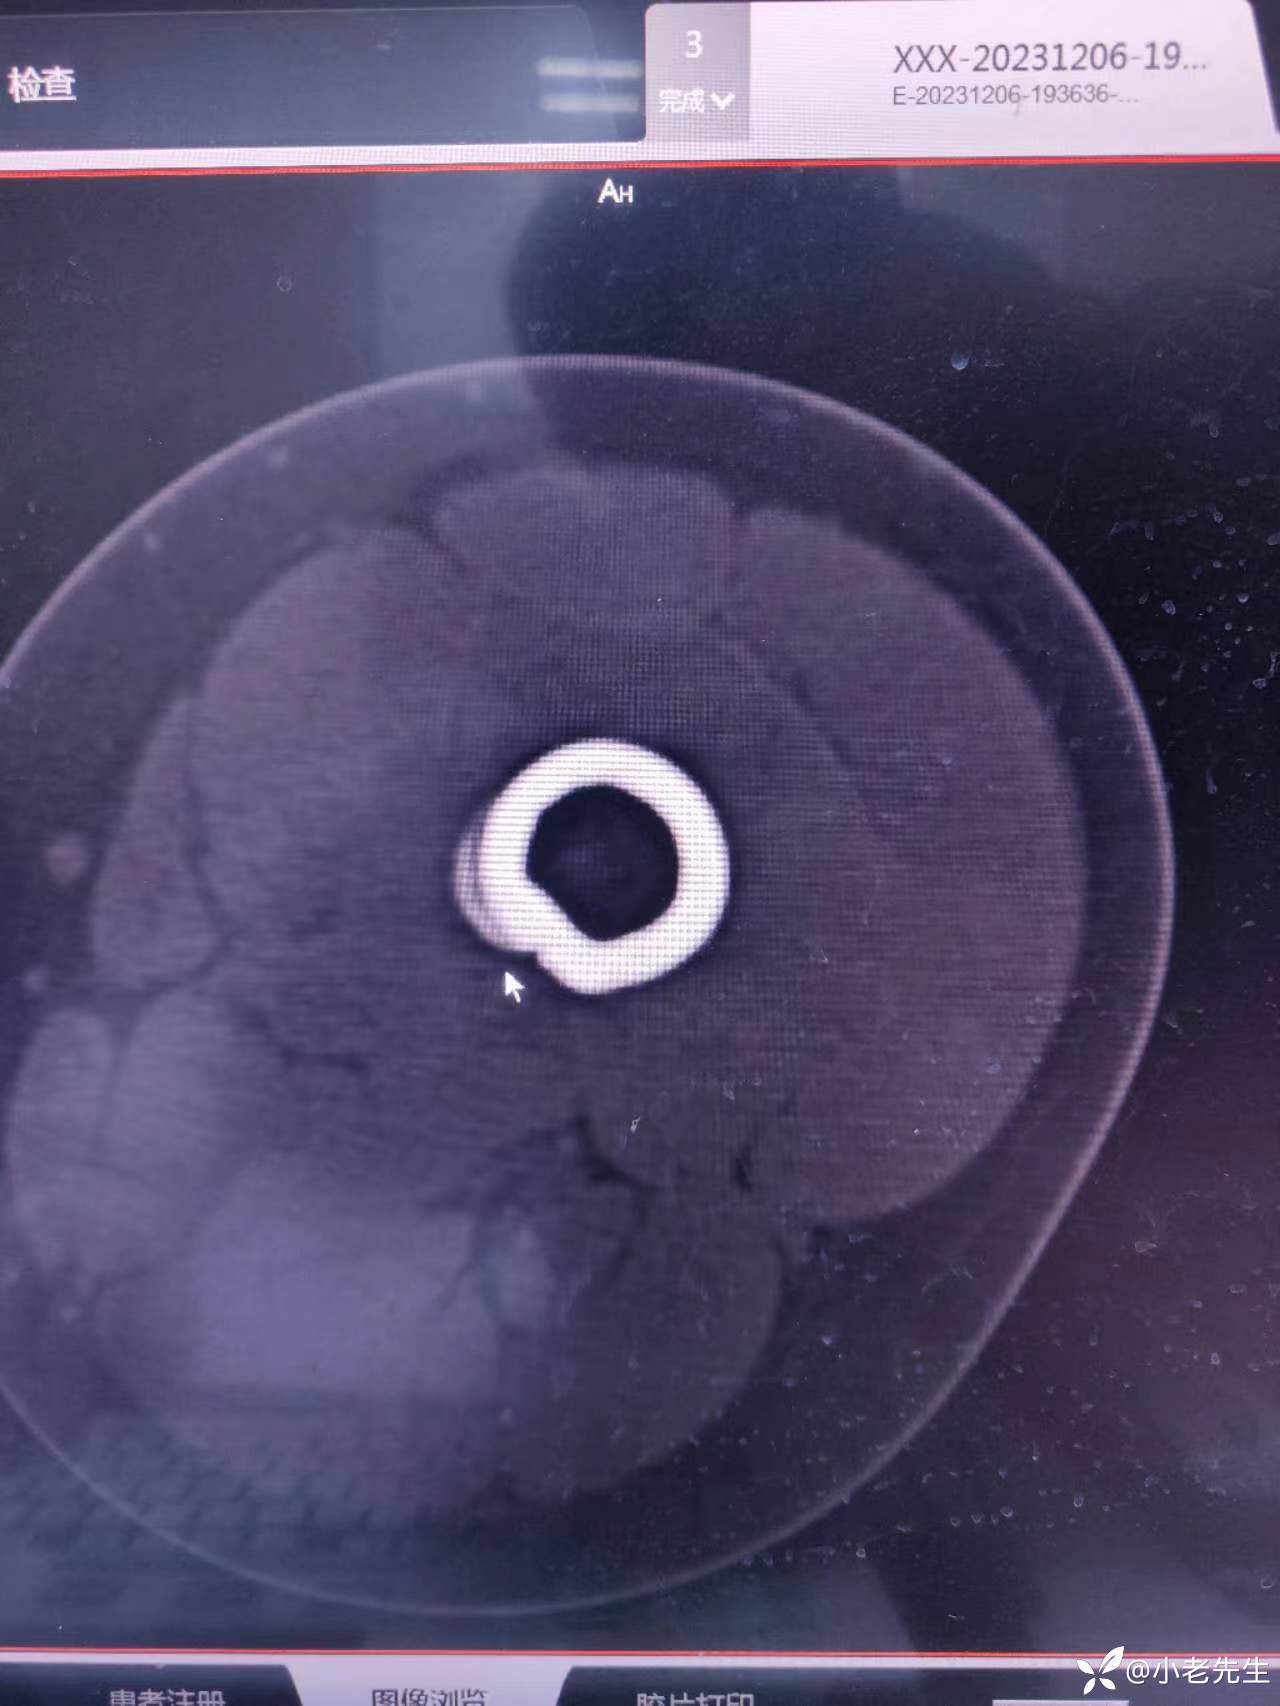

12月6日CT: